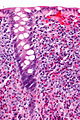

Eosinophilic colitis. H&E stain. | |

| LM | abundant eosinophils - no agreed upon number - "most use 20/HPF", there is variation along the large bowel - normal in rectum <10/HPF, normal in cecum <30/HPF |

Eosinophilic colitis, abbreviated EC, is an inflammatory process involving the colon (colitis) characterized by abundant eosinophils.

- Abundant eosinophils - no agreed upon number.